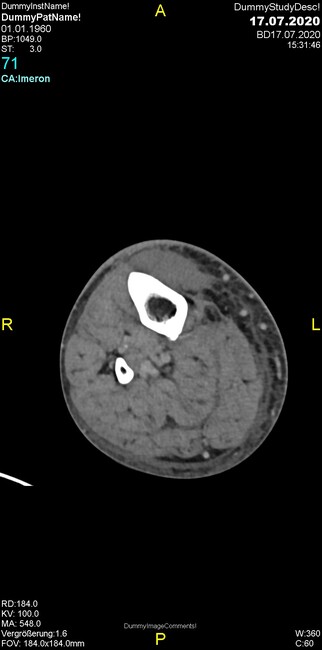

Um welche Modalitäten handelt es sich?

- Röntgen p.a. und lateral, CT coronar Knochenfenster, CT axial Weichgewebsfenster

- Röntgen p.a. und oblique, CT coronar Knochenfenster, CT axial Weichgewebsfenster

- Röntgen p.a. und lateral, CT sagittal Weichgewebsfenster, CT coronar Knochenfenster

- Röntgen p.a. und oblique, CT sagittal Knochenfenster, CT coronar Weichgewebsfenster

- Röntgen p.a. und lateral, CT coronar Weichgewebsfenster, MR axial

Was fällt in der Projektionsradiographie auf?

- Verdichtung im Recessus suprapatellaris

- Aufhellungslinie in Projektion auf die Femurkondylen

- Erhöhter tibialer Slope

- Hypertransparenz tibial

- Subluxationsstellung im Kniegelenk

Was trifft auf den Befund zu?

- Der Befund beschränkt sich auf den Knochen.

- Es besteht hochakuter Handlungsbedarf.

- Der Befund ist tendenziell benigne.

- Der Befund ist tendenziell maligne.

- Der Befund weist einen Zusammenhang zum Patientenalter auf.

Was fällt in der CT im Knochenfenster auf?

- Mediale Gelenkspaltverschmälerung

- Dezente Erosion der fibulären Kortikalis

- Frakturspalt der lateralen Tibiametaphyse

- Weichgewebskalzifikationen lateral angrenzend an den Gelenkspalt

- Osteolyse der Tibiametaphyse unter Beteiligung der Kortikalis